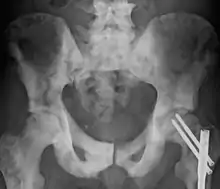

| Sclerosis of the bones of the pelvis due to prostate cancer metastases | |

Osteosclerosis is a disorder that is characterized by abnormal hardening of bone and an elevation in bone density. It may predominantly affect the medullary portion and/or cortex of bone. Plain radiographs are a valuable tool for detecting and classifying osteosclerotic disorders.[1][2] It can manifest in localized or generalized osteosclerosis. Localized osteosclerosis can be caused by Legg–Calvé–Perthes disease, sickle-cell disease and osteoarthritis among others. Osteosclerosis can be classified in accordance with the causative factor into acquired and hereditary.[2][1]

Osteosclerosis can be detected with a simple radiography. There are white portions of the bone which appear due to the increased number of bone trabeculae.